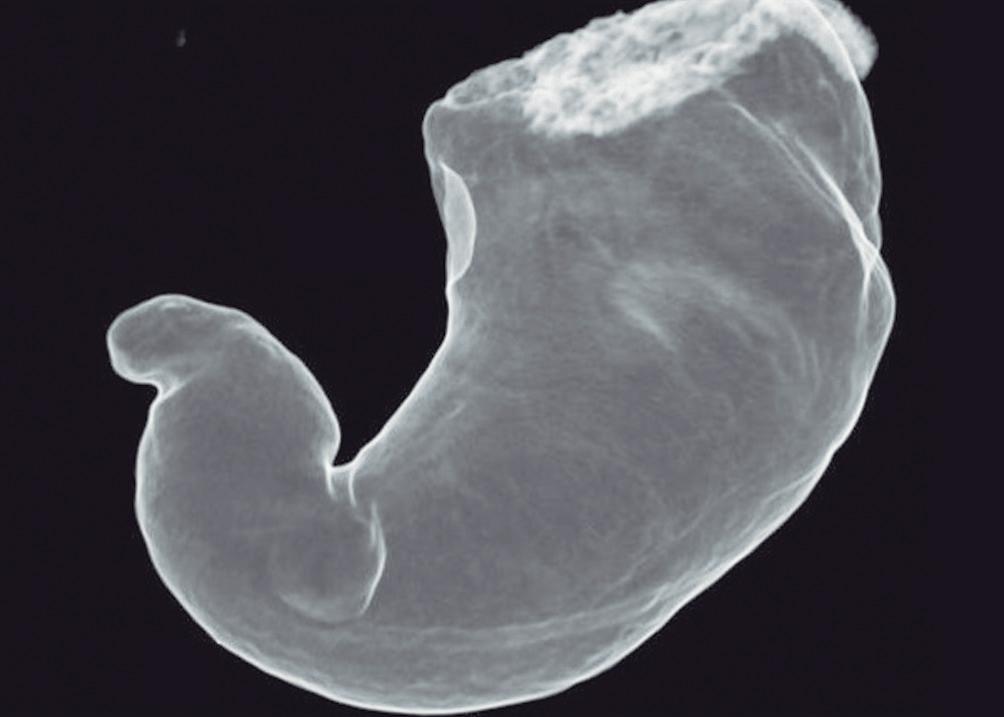

Evaluación de un paciente con dolor epigástrico y hallazgos sincrónicos infrecuentes

Roy López Grove, Daniela Soloaga, Juan Carlos Spina

Roy López Grove, Daniela Soloaga, Juan Carlos Spina 398